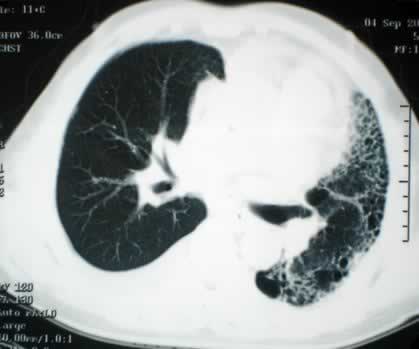

在35年前的今天,1986年10月28日(农历1986年9月25日),心肺同时移植首次在西班牙完成。1986年10月28日,西班牙潘普洛纳市纳瓦拉大学医院成功地进行了一次心脏和肺脏同时移植手术。这一手术在西班牙是第一次。接受心肺植入手术的是十三岁的女孩阿尔穆德纳-加尔韦斯,她因双肺纤维性病变,呼吸十分困难。这家医院心血管外科专家二十七日午夜开始对女孩施行移植手术,手术复杂艰难,持续到二十八日凌晨四点。据手术医生说,手术后女孩感觉良好。植入女孩的心脏和肺脏取自一位十一岁的男孩,他是不幸因脑颅创伤死亡的。据报道,截止一九八五年,全世界共作过一百零八例心肺同时移植手术,其中绝大部分是在美国和英国进行的。美国是世界上第一个心肺同时移植手术获得成功的国家。人类文明的见证